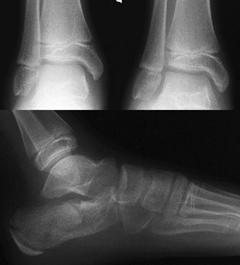

TRAUMATISMELE EXTREMITATILOR

Fracturi simple: SPIRALA OBLICA TRANSVERSALA

Fractura spirala de Fractura transversa de diafiza femurala Fractura spirala de diafiza tibiala

Fractura spirala de diafiza tibiala Fractura oblica de diafiza tibiala Fractura transversala de diafiza tibiala